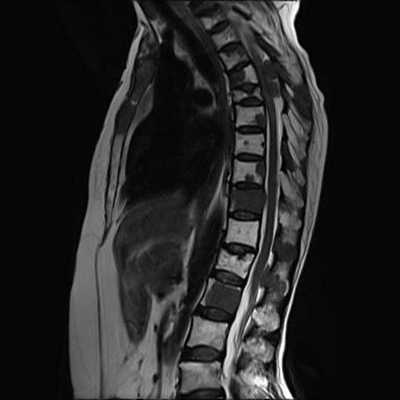

Признаки грыжи на МРТ

Часто при необходимости обследовать спину на томографе пациенты интересуются вопросом: а сможет ли врач увидеть на МРТ снимке межпозвоночную грыжу. Можно уверенно ответить - да, именно магнитно-резонансное исследование очень точно определяет эту патологию. На томографических изображениях невролог сможет не только четко увидеть локацию этой патологии, но и оценить все ее параметры - размер, степень выбухания в позвоночный канал и меру сдавливания нервных окончаний.

Даже любопытствующий пациент при желании сам сможет увидеть МР картину грыжевого образования. Ему на МРТ снимке нужно искать небольшой выступающий сегмент между позвонками. Выпячивание грыжи будет тем сильнее, чем дольше она присутствует у пациента. Побочным признакам грыжи станет деформация пульпозного ядра и снижение объема цереброспинальной жидкости.